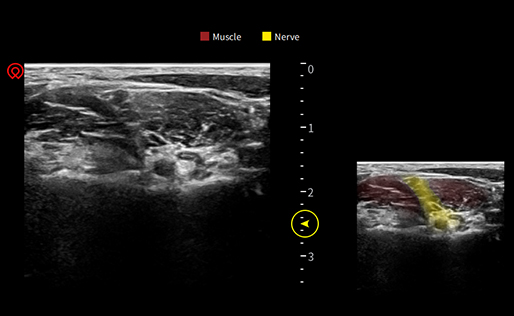

wiNerve

AI Intelligent Nerve Recognition

Real-time Recognition

Cloud Solution

Support Multiple Nerves